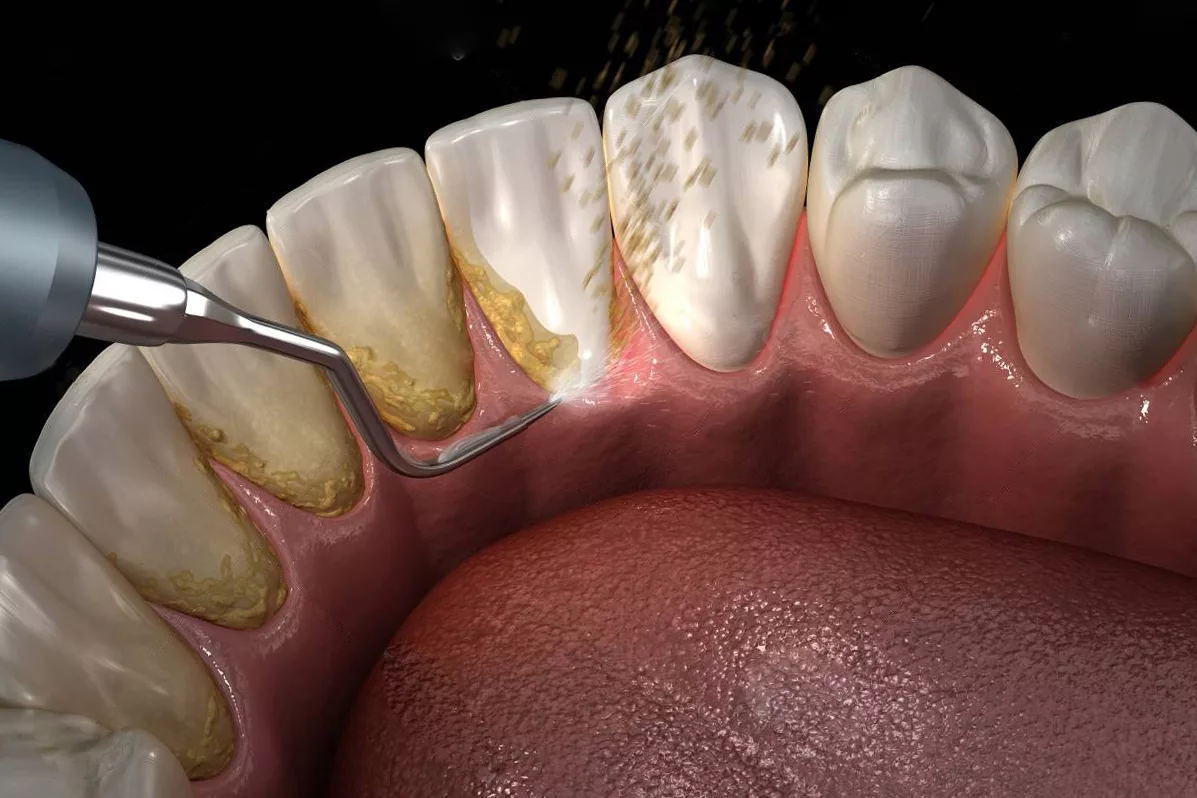

Профессиональная чистка зубов

Профессиональная чистка зубов у стоматолога — это важная мера профилактики. Врач сможет удалить зубной камень, который уже образовался, и провести глубокую чистку, недоступную для домашнего ухода. Рекомендуется проходить профессиональную чистку не реже двух раз в год.